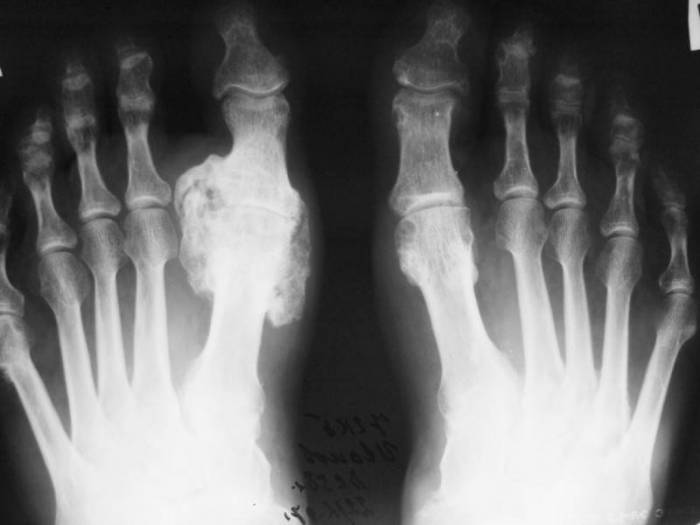

Рентгеновские проявления суставного заболевания в первую очередь наблюдаются по краям костных структур. Они приобретают вид своеобразной раковины или скорлупы. Существует целая классификация стадий по признакам подагры, которые можно увидеть на рентгене:

- Первая стадия. В пораженном месте формируются кисты и скопления уратов. Наблюдается уплотнение мягких тканей.

- Вторая стадия. В области сустава образуются характерные для патологии крупные по размеру кисты. Также начинаются эрозивные процессы на поверхности сочленения.

- Третья стадия. Ткани подвергаются сильной эрозии. Она может занимать около трети всего сустава. В результате этого происходит частичное разрушение кости и отложение в пустых полостях кристаллов солей.

Рентгенологические изменения обычно наблюдают при течении 1-й и 2-й стадии подагрического артрита. Они образуются на протяжении 9 лет. Примерно через 10-15 лет в области сустава происходят необратимые разрушения. Если пациент своевременно начнет правильно лечить свое заболевание, то ему удастся избежать негативных последствий и серьезных осложнений, которые даже могут привести к инвалидности.